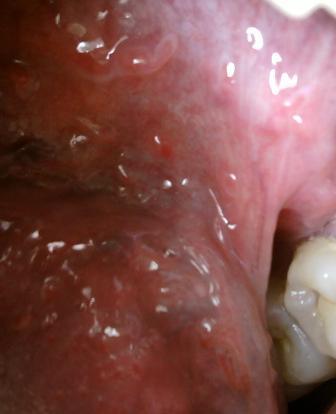

尖锐湿疣会对男性带来怎样的危害尖锐湿疣性病如果不及时治疗,将会对人体健康嗲来严重的危害,适合自身病情的治疗方法就是最佳疗法,尖锐湿疣这种顽固性的疾病,患病之后应该及时选择一家比较权威的医院进行治疗,锐湿疣的发生主要是由人类乳头瘤病毒所致,常发生在肛门及外生殖器等部位,其传染途径主要通过性行为传染。现在尖锐湿疣性病是比较多发的,所以及时做好疾病的预防工作很关键,预防尖锐湿疣的措施,不熬夜,生活规律。不劳累,精神状态良好。坚持治疗才可以达到很好的治疗疾病的目的。